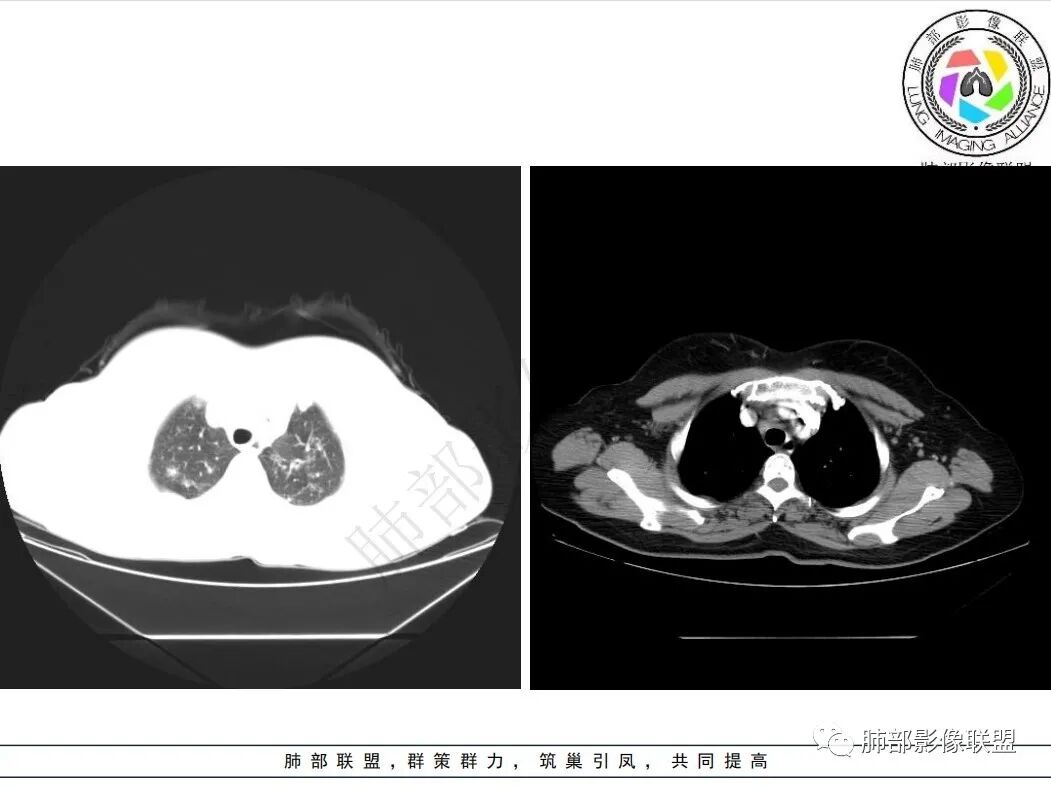

双肺以双肺上叶分布为著多发结节,粟粒,斑片影,边缘部分模糊,部分病灶沿纹理走形分布,中轴间质增厚,纵隔及肺门淋巴结肿大。考虑结核?结节病?

双肺中轴间质增厚,双肺可见多发结节影,沿支气管血管束及小叶间隔胸膜下分布为主,纵膈淋巴结肿大,考虑淋巴增殖性病变,结节病?

图像太小,双肺多发结节,淋巴道分布,纵膈多发淋巴结增大,结节病?

中老年女性,中轴间质增厚,双肺多发结节,沿淋巴道分布,考虑结节病,鉴别血管炎

双肺多发大小不等结节,上叶为著,似有淋巴分布特点。右肺中轴间质增厚,支气管受压变窄。纵隔、右侧腋窝及肺门多发淋巴结明显肿大。

中年女性,查体发现,两肺多发结节,沿支气管血管束及胸膜下分布,右肺中轴间质增厚,两肺门、纵隔及右侧腋窝轻度肿大淋巴结,考虑结节病

中年女性,体检发现,双肺沿支气管血管束分布多发结节影,小叶间隔增厚,纵隔内淋巴结肿大,考虑淋巴增殖性病变,结节病可能

双肺多发中央间质及小叶间隔增厚,并见多发小结节影,沿支气管血管束分布,伴纵隔增大淋巴结,考虑淋巴道增殖病变,结节病

2.双肺小叶间隔及中轴间质增厚,多发结节沿小叶间隔及支气管血管束分布,纵隔、右侧腋窝及左肺门多发淋巴结增大。